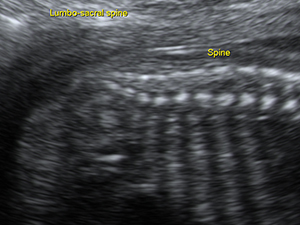

Fetal spine in the second trimester Abdomen